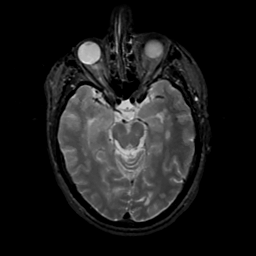

MR Study #16, June 23, 1991 -- Slice #19